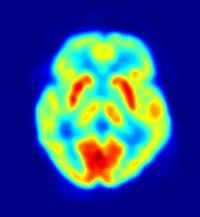

cerveau en fonctionnement